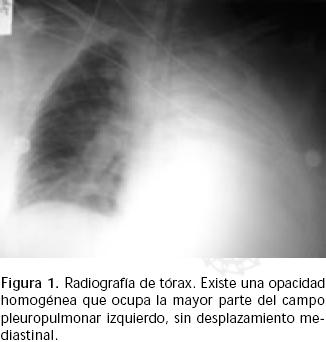

Hombre de 70 años de edad, tabaquismo de cinco paquetes año, con hipertensión arterial sistémica (HAS) de 20 años de evolución, tratado irregularmente con enalapril. A los 58 años de edad desarrolló enfermedad cerebrovascular hemorrágica, que dejó como secuela hemiplejía corporal izquierda. Posteriormente, en forma súbita presentó hemoptisis masiva de más de 500 mL en 24 h7,8 por lo que fue ingresado al hospital en estado de choque con diaforesis, palidez e hipotensión arterial severa. Se tomó radiografía de tórax (Figura 1). La esofagogastroscopía demostró esófago normal y gastritis erosiva sin sangrado. Recibió cristaloides, coloides y hemoderivados, con lo que mejoraron sus condiciones clínicas; persistió expectoración hemoptoica.